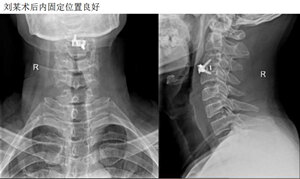

另附一脊髓型颈椎病病例

刘某,男,45岁,双上肢麻木、乏力2月,入院行前路颈椎间盘摘除植骨融合内固定术,术后症状缓解。